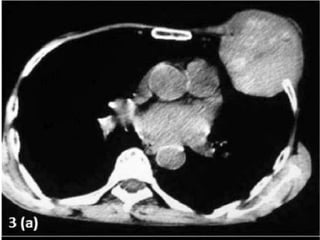

Hcc with sternal mets presentation

• 1.

UNUSUAL PRESENTATION OF HCC DR. RAJKUMAR, R. III YR POST GRADUATE DR. KALAICHELVI D.M. H.O.D. & PROF DEPT. OF MEDICAL ONCOLOGY MADRAS MEDICAL COLLEGE CHENNAI

• 2.

MR . X60/ M REFERRED FROM SGE I C/O SWELLING OVER THE ANT. CHEST WALL – 6 MONTHS . H/O PAIN FOR THE PAST- 2 WEEKS. NON ALCOHOLIC/ BEEDI SMOKER

• 3.

10×7 CM MASSOVER THE ANT. CHEST WALL FIRM IN CONSISTENCY P/A- HEPATOMEGALY

• 4.

INVESTIGATIONS • CBC- NORMAL •LFT- S. BILIRUBIN- 1.3 DIRECT- 0.9 ALK.POS- 80 T.PROT- 6.8 ALB- 3.7 • RFT- NORMAL • HbSAG- NEGATIVE • ANTI HCV- NEGATIVE • HIV I & II- NEGATIVE • ALPHA-FETO PROTEIN- 1.62 IU/ml • USG ABDOMEN- HETEROECHOIC LESION RIGHT LOBE OF LIVER-11.5×10.5 CM – • IMPRESSION- HCC Rt. LOBE OF LIVER

• 14.

HCC – METASTATIC •UNUSAL EXTRA HEPATIC METASTATIC SITE • NON CIRRHOTIC BACKGROUND • GOOD P.S. STATUS • BCLC STAGE C • SORAFENIB – 200 MG B.I.D. • PALLIATIVE R.T. - STERNUM